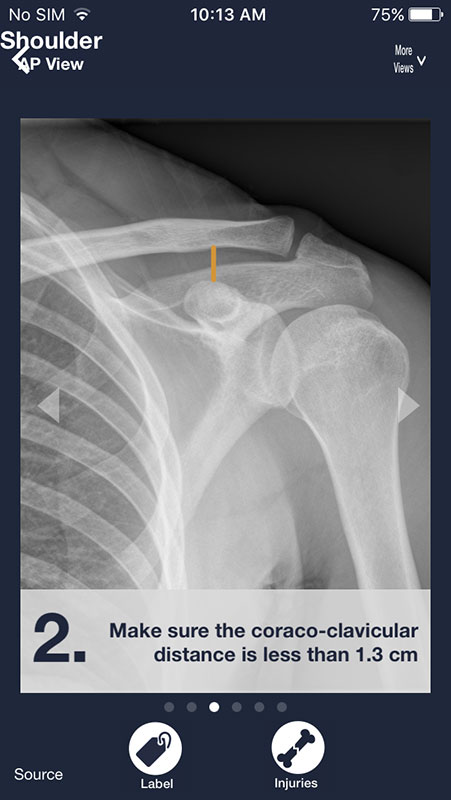

You can swipe the screen to navigate through the series of images. Each following image is annotated and contains a piece of advice on what to look for on a radiograph in order to distinguish between normal anatomy and abnormalities/pathologies.

There are two buttons below each image. First, Label button annotates the structures in the first image, showing them in different colors with names.